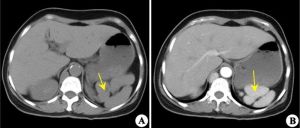

1.有一個或多個副脾。為結節狀或球狀的組織,密度或增強特性與正常脾臟相同。